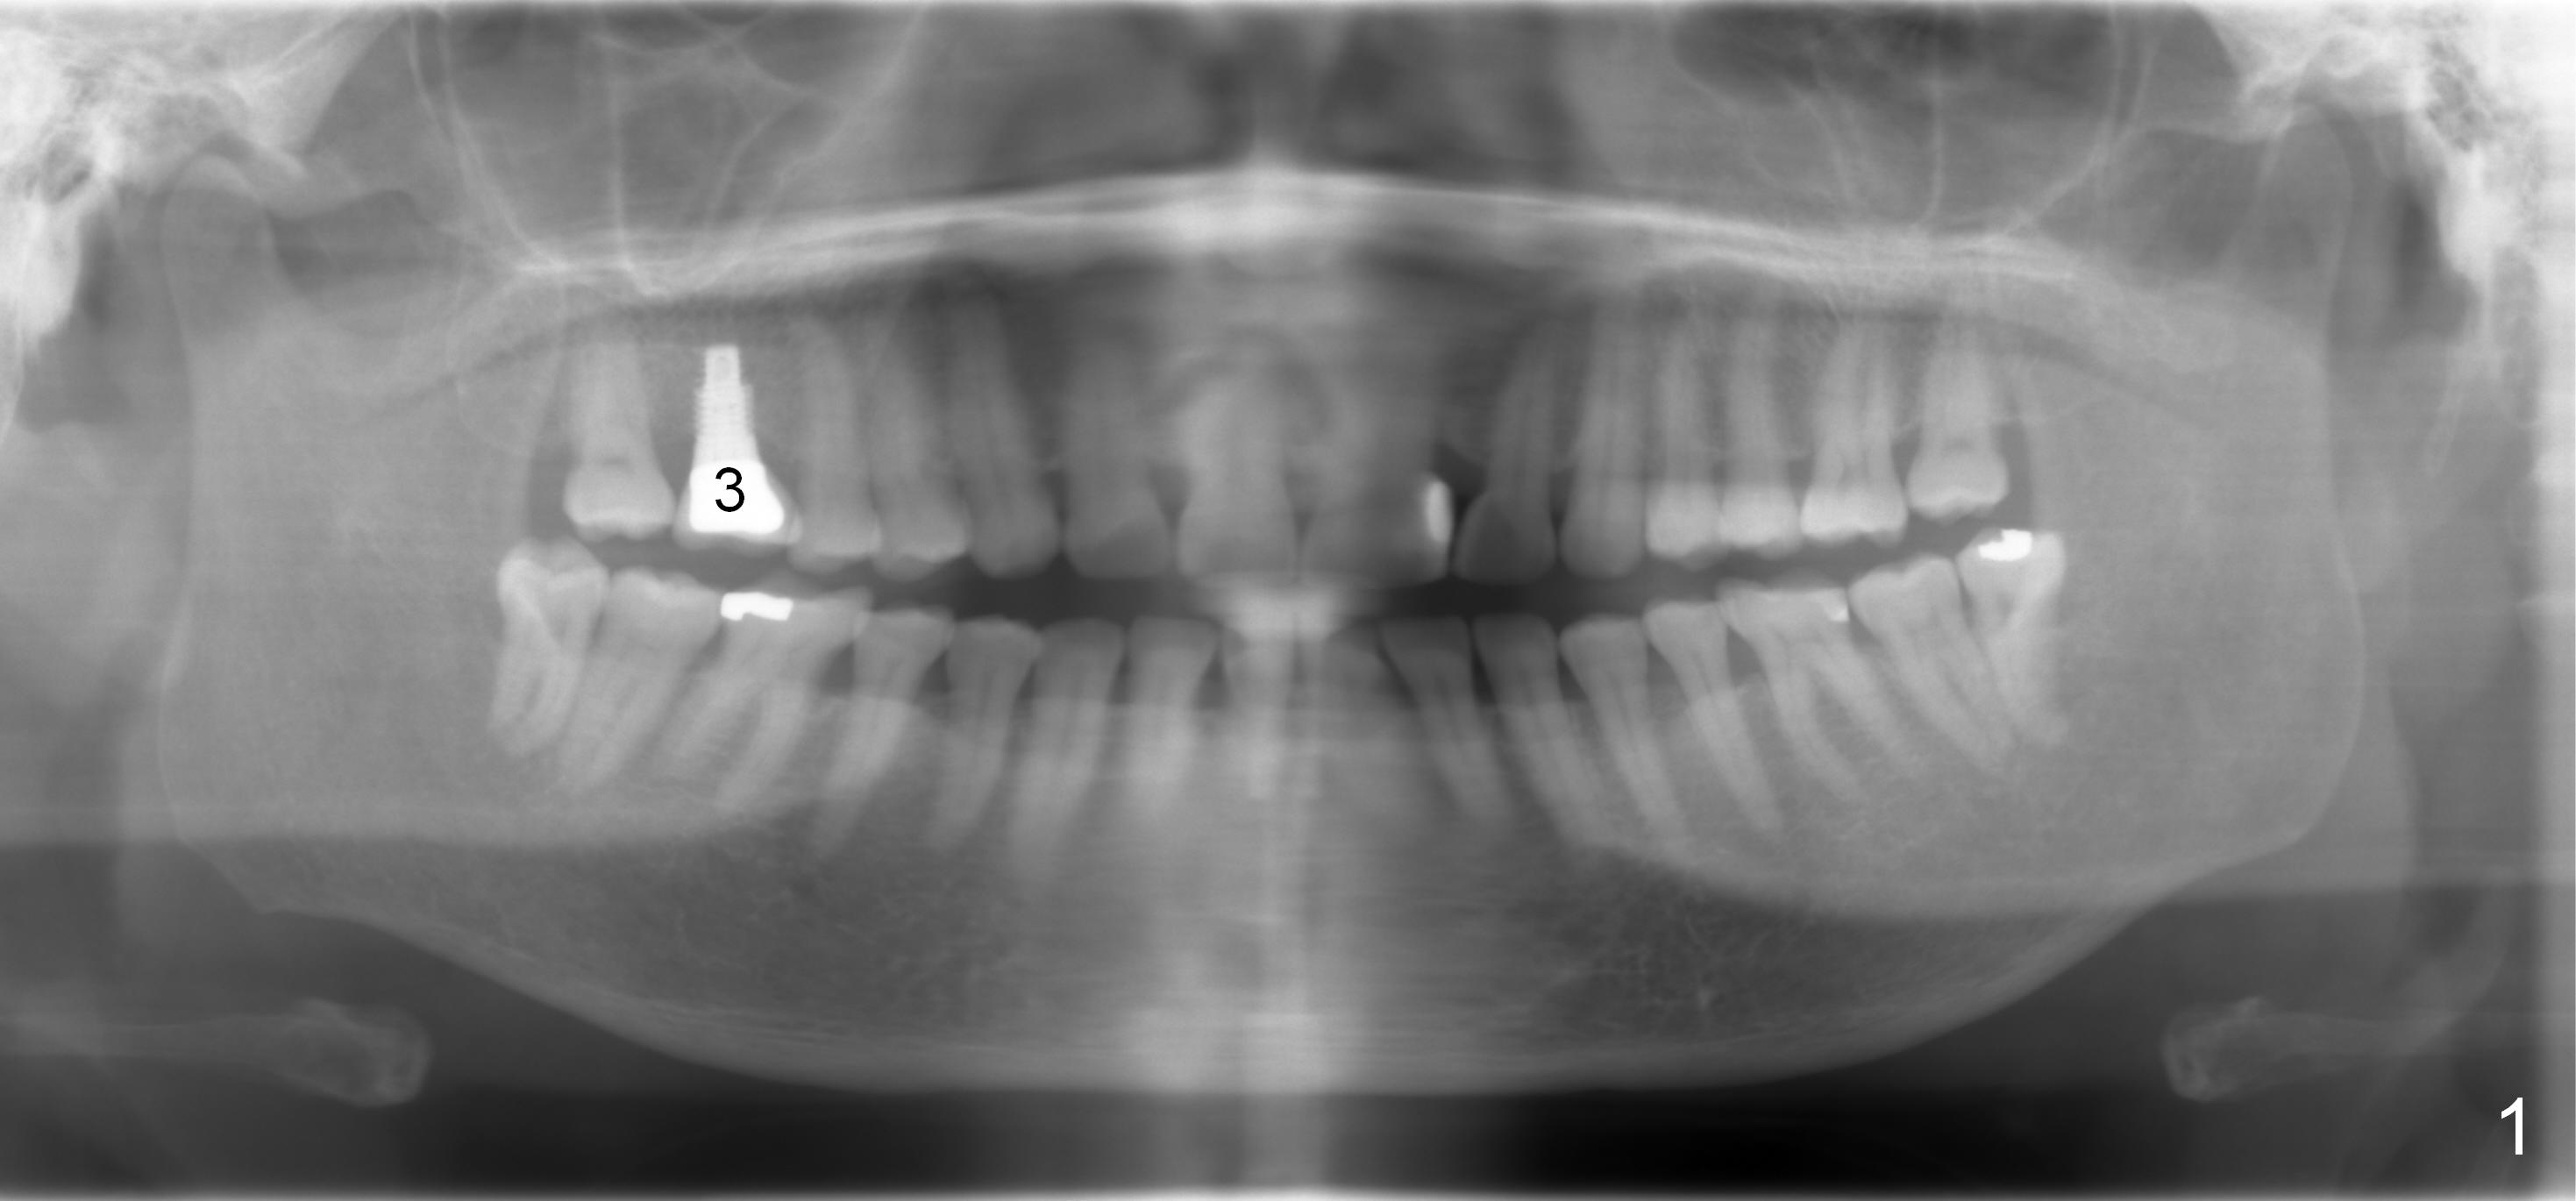

A 67-year-old lady (CC) has an implant at the site of #3, which replaces the fractured tooth (Fig.1). Recently the tooth #13 also fractures subgingivally (Fig.2). The tooth has a long and curved root. All of these suggest that the patient is a bruxer. The bone density is high. After extraction and placement of Clindamycin gauze in the socket, a 2 mm pilot drill is used to start osteotomy ~17 mm from the gingival margin, followed by 2.5 mm reamer ~ 17 mm, and 3 for 14 mm. If the socket looks small (mesiodistally), the goal is to place 4.1x14 (Fig.3) or 13 mm (Fig.4) implant. Otherwise use 4.5x17 mm Tatum tapered tap at 14 mm and plan to place a 4.5x13 or 14 mm implant. If it is difficult to insert an implant, use one size smaller drill from its original cassette or use 5x17 mm tap at 11 mm (to open up the entrance of the osteotomy). If the implant or tap is being deviated buccally while it is placed, use a Lindermann bur from Bicon Restorative plastic box to remove the bone from the palatal wall. When the side-cutting drill is cleaned, keep it in the Bicon Surgical Cassette. If the bone density turns out to be low, osteotomy depth will be 20 mm instead (Fig.5). When the flutes of 2.5 and 3 mm reamers collects bone particles, the bone density is high.